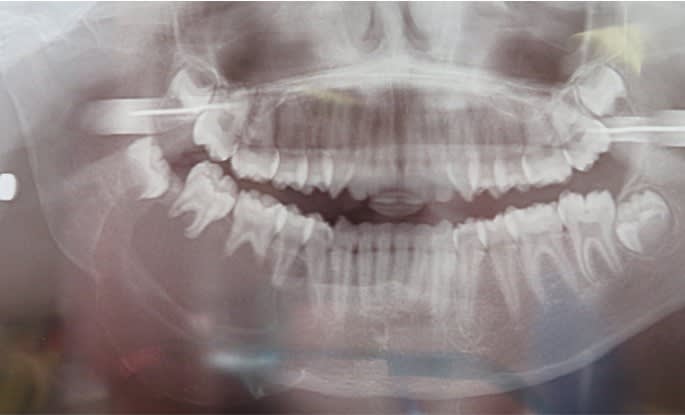

tu proposes ce type de prestation, la mise en charge immédiate en 1 seule intervention avec un bridge à armature métal rigide ???

Et sur ton cas précédent... Quelles sont les indications de l avulsion de 22 11 12 13 ???

un petit kyste

mais ce n'est pas un concours de celui qui pisse le plus loin, il faut juste être cohérant, tu parles de progrès technologie, Quelle plan de traitement tu proposes ?

quelles sont les indications des avulsions de 21 22 23 et 12 ???